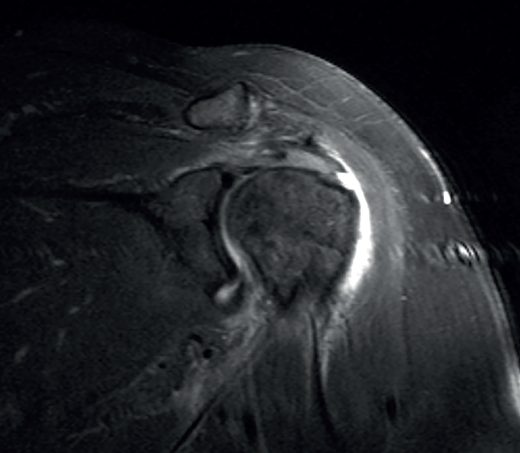

Traditionally, the appearance of rotator cuff disease has been described as a progressive disorder that initially manifests as acute tendinitis, continues as tendinosis with tissue degeneration and partial ruptures, and ultimately results in full thickness rupture(6). The terms tendinitis and tendinosis represent different stages of tendinopathy. Tendinitis refers to acute or chronic pain associated by definition to inflammation, even if the histological studies show an absence or only minimal presence of inflammatory cells(7). Tendinosis in turn refers to degenerative disease with or without inflammation (Figure 1). Tendinopathy is the term used to describe a clinical condition characterized by pain and functional alteration of the tendons of the rotator cuff, without specification of the concrete causal mechanism involved(8).

Figure 1. Arthroscopic view from the posterior portal in a case of severe supraspinatus tendinosis of a left shoulder.